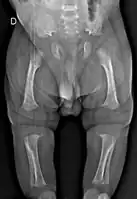

Radiologic findings

A skeletal survey is useful to confirm the diagnosis of achondroplasia. The skull is large, with a narrow foramen magnum, and relatively small skull base. The vertebral bodies are short and flattened with relatively large intervertebral disk height, and there is congenitally narrowed spinal canal. The iliac wings are small and squared, with a narrow sciatic notch and horizontal acetabular roof.[15][16] The tubular bones are short and thick with metaphyseal cupping and flaring and irregular growth plates.[15] Fibular overgrowth is present. The hand is broad with short metacarpals and phalanges, and a trident configuration. The ribs are short with cupped anterior ends.[15] If the radiographic features are not classic, a search for a different diagnosis should be entertained. Because of the extremely deformed bone structure, people with achondroplasia are often "double jointed". The diagnosis can be made by fetal ultrasound by progressive discordance between the femur length and biparietal diameter by age. The trident hand configuration can be seen if the fingers are fully extended.